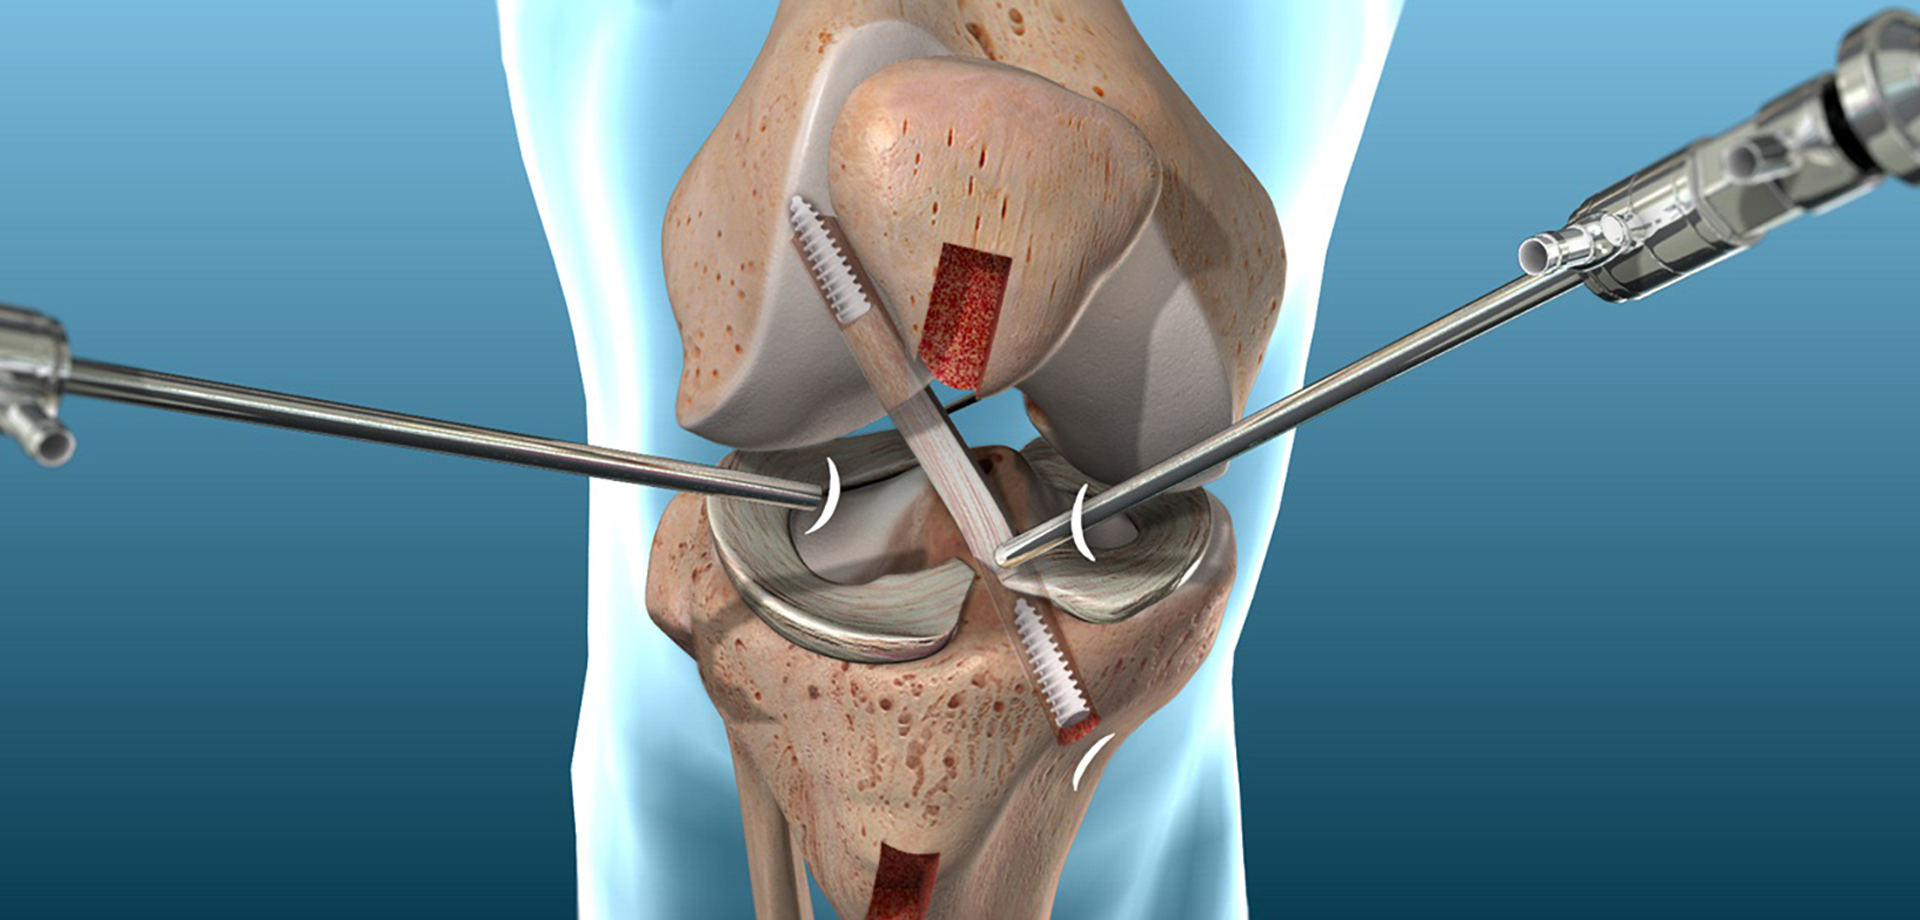

The department offers a full spectrum of non-surgical and surgical orthopedic services, with a strong emphasis on minimally invasive techniques. Advanced procedures such as arthroscopy, minimally invasive and endoscopic spine interventions, and modern fracture fixation methods are used to reduce surgical trauma, minimize pain, and promote faster recovery with shorter hospital stays. These approaches allow patients to return to daily activities and work more quickly, while maintaining high standards of safety and clinical outcomes.

Sports medicine is an integral component of the department’s services. We manage acute injuries, overuse conditions, and degenerative joint problems commonly seen in athletes and physically active individuals. Conditions involving the knee, shoulder, ankle, hip, and spine are treated through a coordinated approach that combines medical management, targeted rehabilitation, and, when necessary, surgical intervention. Rehabilitation programs are carefully structured to restore strength, flexibility, balance, and performance while reducing the risk of re-injury.